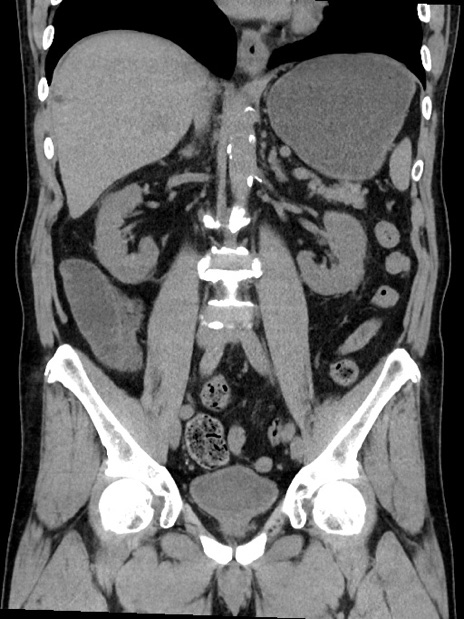

症例35(冠状断像)

【症例】70歳代 男性

【主訴】腹部膨満、嘔吐

【現病歴】昨日より腹部膨満感出現。本日増悪し、仙痛出現。嘔吐あり、受診。

【既往歴】糖尿病、胆摘後

【身体所見】BP 149/80mmHg、HR 74/min、BT 35.9℃、腹部:膨満、軟、圧痛なし。腸雑音減弱あり。上腹部正中切開瘢痕あり。

【データ】WBC 13500、CRP 1.72